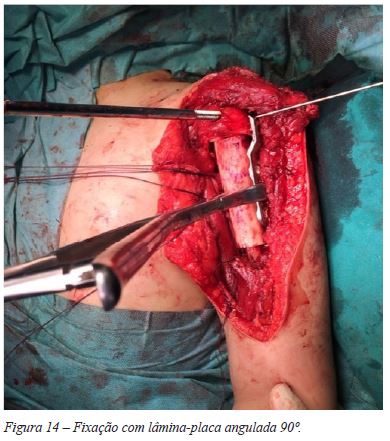

Introduziu-se a lâmina de bisturi na fise, de forma a separar a epífise e metáfise umerais proximais, conseguindo-se uma ressecção monobloco, sem visualização macroscópica do tumor (Figura 13). Colheram-se amostras de tecido ósseo do topo distal do úmero e da zona fisária residual na epífise umeral, tendo-se enviado o material para estudo anatomo-patológico e confirmação das margens de ressecção. De seguida, foi realizada a preparação de enxerto alógeno de úmero - com confecção de corte para encastoar no úmero nativo distalmente e para melhor adaptação a nível epífise. Fixou-se com lâmina-placa 90º, mantendo o cravo proximal para orientação da mesma (Figura 14). A fixação foi reforçada com a aplicação de uma placa recta LCP 3,5mm num plano ortogonal relativamente à outra placa (Figura 15). Ambas as placas foram aplicadas em compressão. Não se registaram intercorrências peri-operatórias.